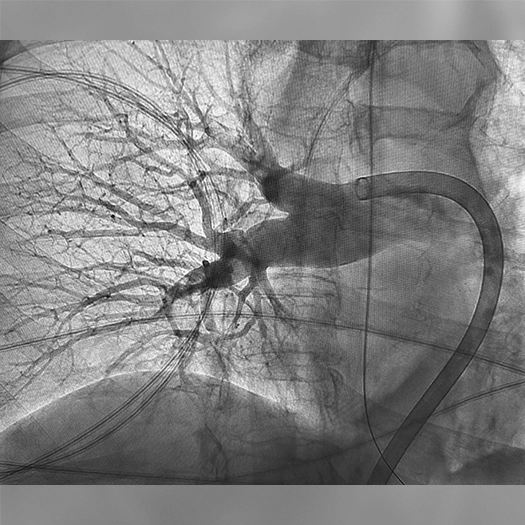

Pulmonary Embolism Cases

Venous Cases

Images used with permission and provided for illustrative purposes only. Procedural techniques and decisions based on physician’s medical judgment. Individual results may vary. Consents on file at Penumbra, Inc.